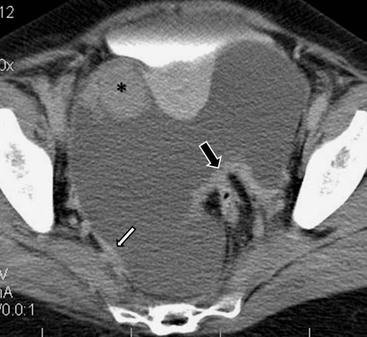

Hydatid disease is most commonly due to Echinococcus granulosus. Peritoneal hydatidosis is usually the result of traumatic or surgical rupture of hepatic hydatid disease and results in cystic, usually septated, thin-walled space-occupying lesions.12 CT is the method of choice in peritoneal seeding (Fig. 30-6). A calcifying rim is a suggestive feature. Ultrasound is useful for the detection of membranes, septa and hydatid sand within the cyst.